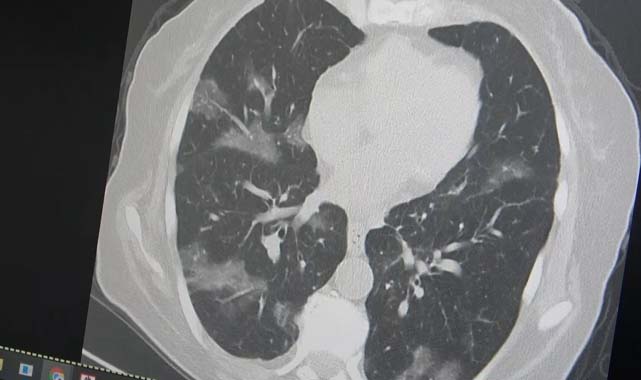

Flirt varyantının Türkiye'de en sık kalan omicron ailesinin bir varyantı olduğuna dikkat çeken Özkaya, "Virüsü de hastalığı da tedavisini de biliyoruz. Test yapmaya gerek yok. Elbet ülkemize de bu varyant gelecek. Flirt insanlarda uzamış şikayetlere neden oluyor. Bir gün iyisiniz, bir gün kötüsünüz. Bir gün çok iyi kalkıyorsunuz, bir gün eklem ağrıları, halsizliğiniz başlıyor. Öksürüğünüz bir türlü geçmiyor. Tam adına uygun bir şekilde flört eder gibi dalgalanmalarla seyrediyor. Son günlerde özellikle Covid-19'un ilk başında gördüğümüz vakalar gelmeye başladı. İlk başlarda akciğer tutulumlar çok görüyorduk. 2024 yılı başından itibaren neredeyse hiç akciğer tutulumu görmemiştik ama bu son günlerde vakalar gelmeye başladı. Özellikle kanser hastaları risk altındadır. Kemoterapi alan, vücut direnci düşük kişiler akciğer tutulumu ile geliyorlar. Özellikle yurt dışı tatilinden ve hacdan dönen kişilerin yaşlı ve vücut direnci düşük kişilerle bir araya gelmesini önermiyoruz” şeklinde konuştu. Kanser hastası bir kişinin akciğerleri üzerinde örnek veren Özkaya, “60 yaşının üstünde olduğu ve kemoterapi aldığı için virüsün kolayca ciğerlere indiğini görüyoruz. Bu yaza damgasını vuracak yeni virüsün bu olduğunu düşünüyoruz” ifadelerini kullandı.